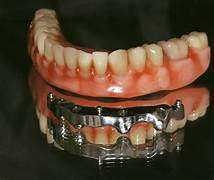

- Phục hình răng: Đọc cung răng giúp nha sĩ thiết kế và chế tạo các loại bảo vệ (như mão răng, cầu răng) phù hợp với hình dạng cung răng.

- Cấy ghép Implant: Đọc cung răng giúp nha sĩ xác định vị trí đặt Implant chính xác, đảm bảo chức năng ăn bột và thẩm mỹ.